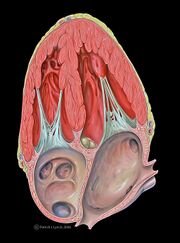

| 12:25, 7 February 2012 | Heart apical 2chamber.jpg (file) |  |

228 KB | {{Information |Description = Heart apical two-chamber echocardiography view |Source = Patrick J. Lynch, medical illustrator |Date = 2006-12-23 |Author = Patrick J. Lynch, medical illustrator |Permission = Creative Commons Attribution 2.5 License 2006 |oth | 1 |